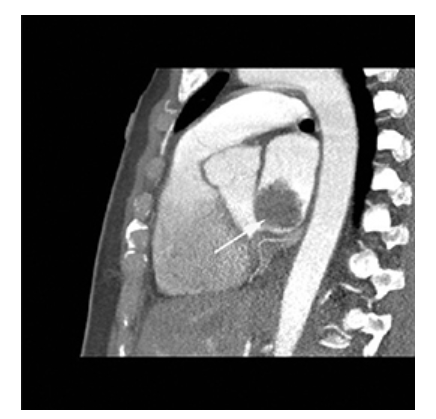

Coronary Artery Disease. Nonenhanced CT (NECT) shows computer-aided detection and calculation of coronary artery calcification in the right coronary artery left circumflex artery

Coronary Artery Disease. Nonenhanced CT (NECT) shows computer-aided detection and calculation of coronary artery calcification in the right coronary artery and left anterior descending coronary artery

Coronary Artery Disease. Nonenhanced CT (NECT) shows computer-aided detection and calculation of coronary artery calcification in the right coronary artery